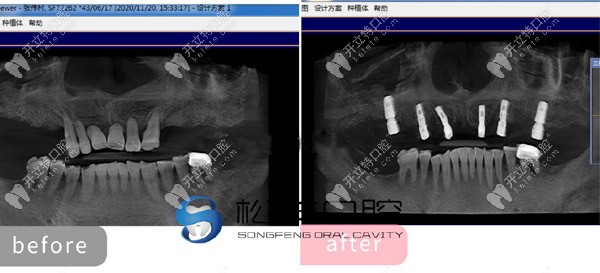

★ 顧客下頜多顆缺失,

上海松豐齒科的蔣院長采用了即刻種植技術(shù),讓顧客當天就了下半口牙。

下頜即刻種植

★ 多顆牙齒缺失種植展示

多顆牙齒缺失種植展示

★ 上半口做了6顆即刻負重種植牙的CT片

上半口做了6顆即刻負重種植牙的CT片

通過這些真人的種植圖,可以看出。上海松豐口腔的種植技術(shù)真的不是吹的!但有人還質(zhì)疑上海松豐齒科正規(guī)嗎,這我可得來說道說道了!